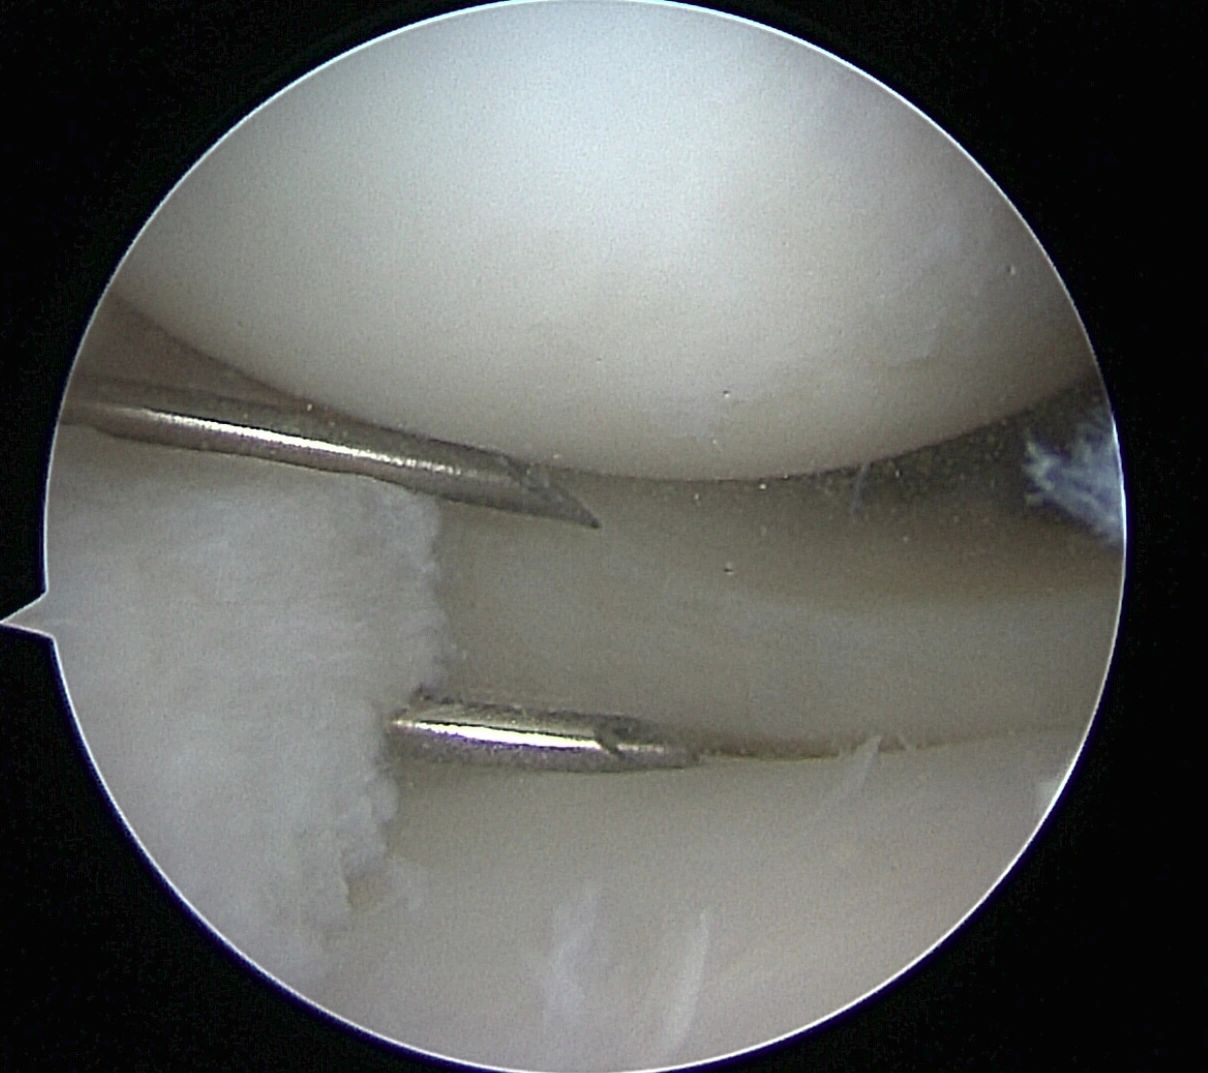

- Meniscus Surgery

- Meniscus Surgery 2